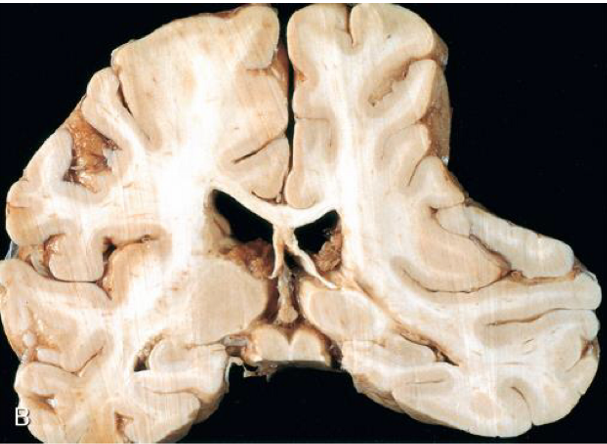

the pathogenesis of the condition seen in the image arises from defective ___ of \_\_\_\_

the pathogenesis of the condition seen in the image arises from **defective cleavage** of **transmembrane cellular proteins**

on histology of the condition seen in the image, ____ proteins accumulate intracellularly, while ____ accumulate extracellularly

on histology of the condition seen in the image, **Tau proteins (neurofibrillary tangles)** accumulate intracellularly, while **A-B amyloid plaque** accumulate extracellularly

describe the presentation of the condition seen in the image

**slowly progressive dementia** (impaired cognition) but motor & sensory intact **start with short-term memory loss** (temporal) → paralysis & bed-ridden (frontal & parietal)

on CT scan of the condition seen in the image, there is flattening of ___ with enlarged \_\_\_\_

on CT scan of the condition seen in the image, there is **flattening of sulci & gyri** with **enlarged ventricles**

the most common cause of death in the condition seen in the image is \_\_\_\_

the most common cause of death in the condition seen in the image is **aspiration pneumonia**

describe how a complication of the condition seen in the image is lobar hemorrhages

**cerebral amyloid angiopathy** = deposition of amyloid in the walls of cerebral vessels